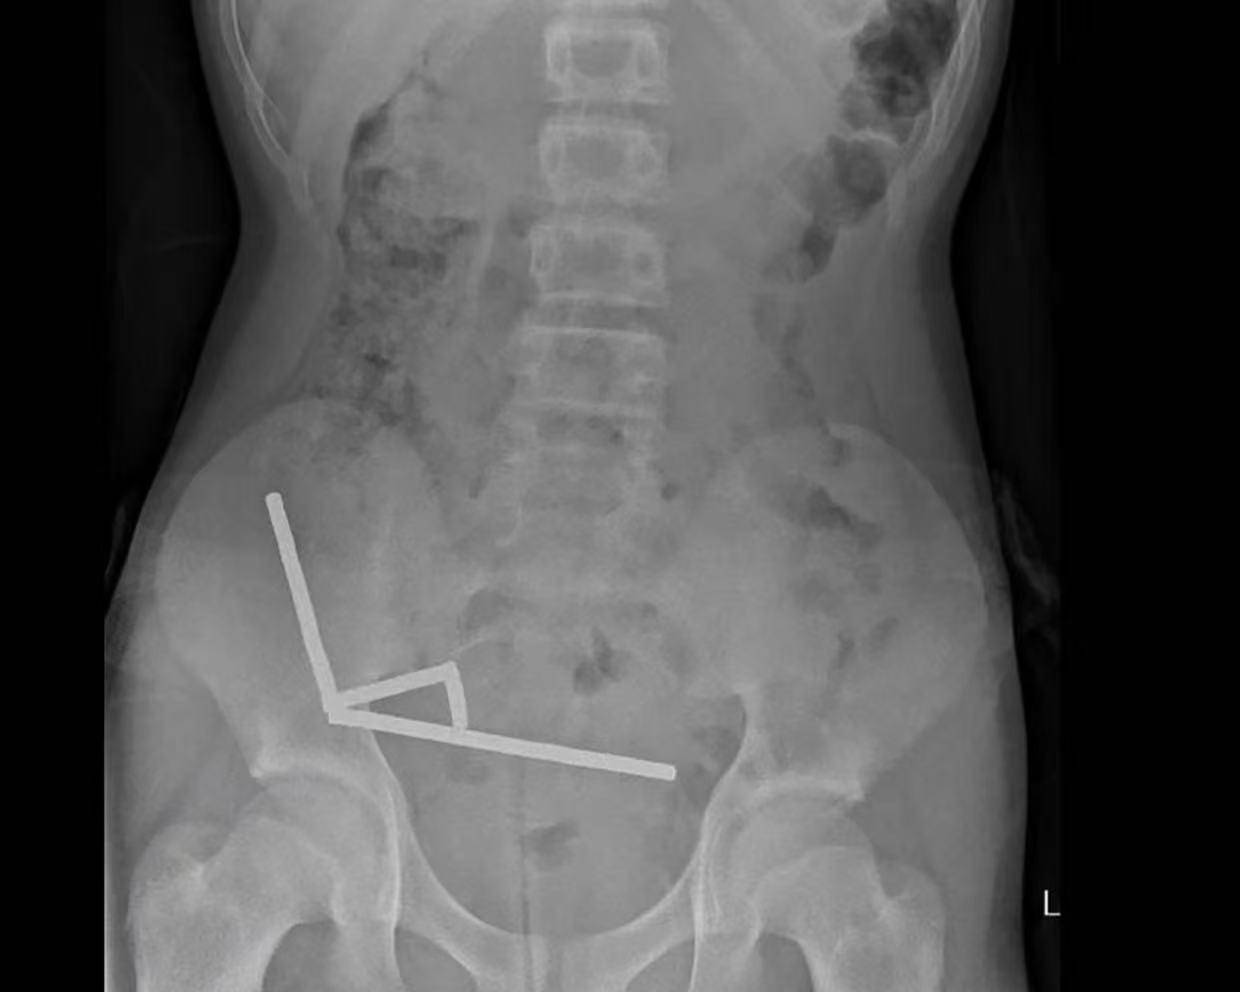

据悉,这名未透露姓名的少年在持续腹痛4天后被送往新西兰北岛的一家医院。医生通过X光检查发现,这些磁铁在他的肠道内互相吸附,形成了四条链状结构。

▲X光显示,磁铁在男孩体内紧密吸附成链状结构

据该院医生于周五在《新西兰医学杂志》上发表的报告称,外科医生取出了磁铁并切除了部分受损的肠组织。磁铁的吸力导致男孩小肠及盲肠(属大肠的一部分)出现四处组织坏死。该男孩在住院8天后康复出院。

医生介绍,男孩大约一周前吞下了80至100颗大功率钕磁铁,每颗尺寸为5×2毫米。报告称,这些磁铁通过一家跨境电商平台购买。